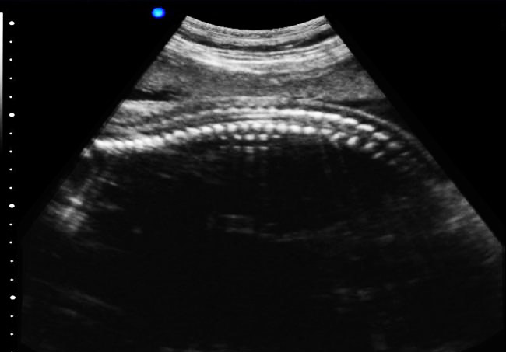

P5-VET獸用彩超機脊椎檢查圖

脊椎檢查:

脊柱裂的預防和確診,一般在動物懷孕以后定期給動物做超聲檢查,通過超聲、超聲檢查可以早期發(fā)現(xiàn)動物胎兒是否合并了脊柱裂或是神經管閉合不全。